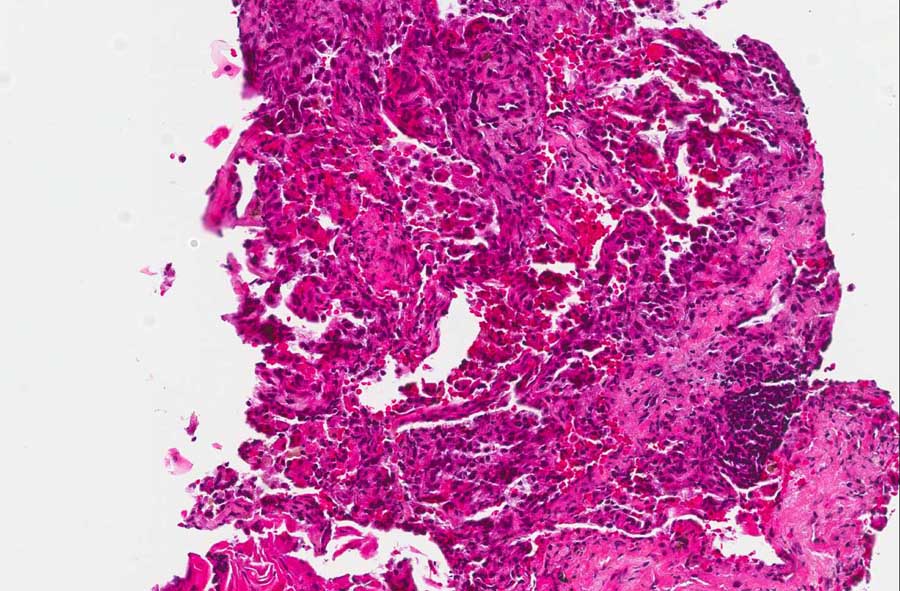

2: Note that other areas are involved by the tumor but, in addition,

there are also foamy macrophages (arrow) |

In some areas of the the specimen, some

foamy cells are present and are likely to represent foamy

macrophages. They are rather common in lung alveoli distal to

obstruction of the corresponding bronchus. As lung cancer often

generates this kind of obstruction, foamy histiocytes are rather

common. (area 2)